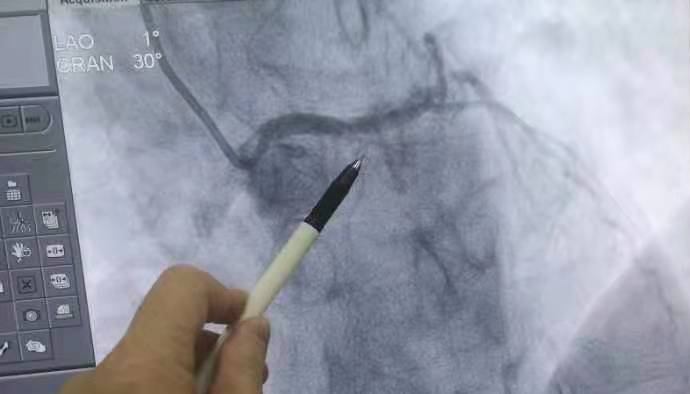

心脏血管闭塞(术前)图示